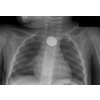

ON-LINE kurz: Z pohodlí domova a kdykoli znovu, zásady první pomoci u dětí. Vše od otrav, popálenin či pádů, přes alergické reakce, krvácení, spolykané hračky, až po akutní stavy jako je dušení a základy neodkladné resuscitace. Už vás nevyděsí laryngitidy ani febrilní křeče a zaskočení sousta jídla.